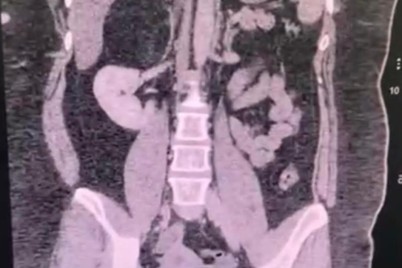

مكة المكرمة ـ إبراهيم البلوشي نجح فريق طبي بمستشفى النور التخصصي عضو تجمع مكة المكرمة الصحي من استئصال ورم يبلغ...